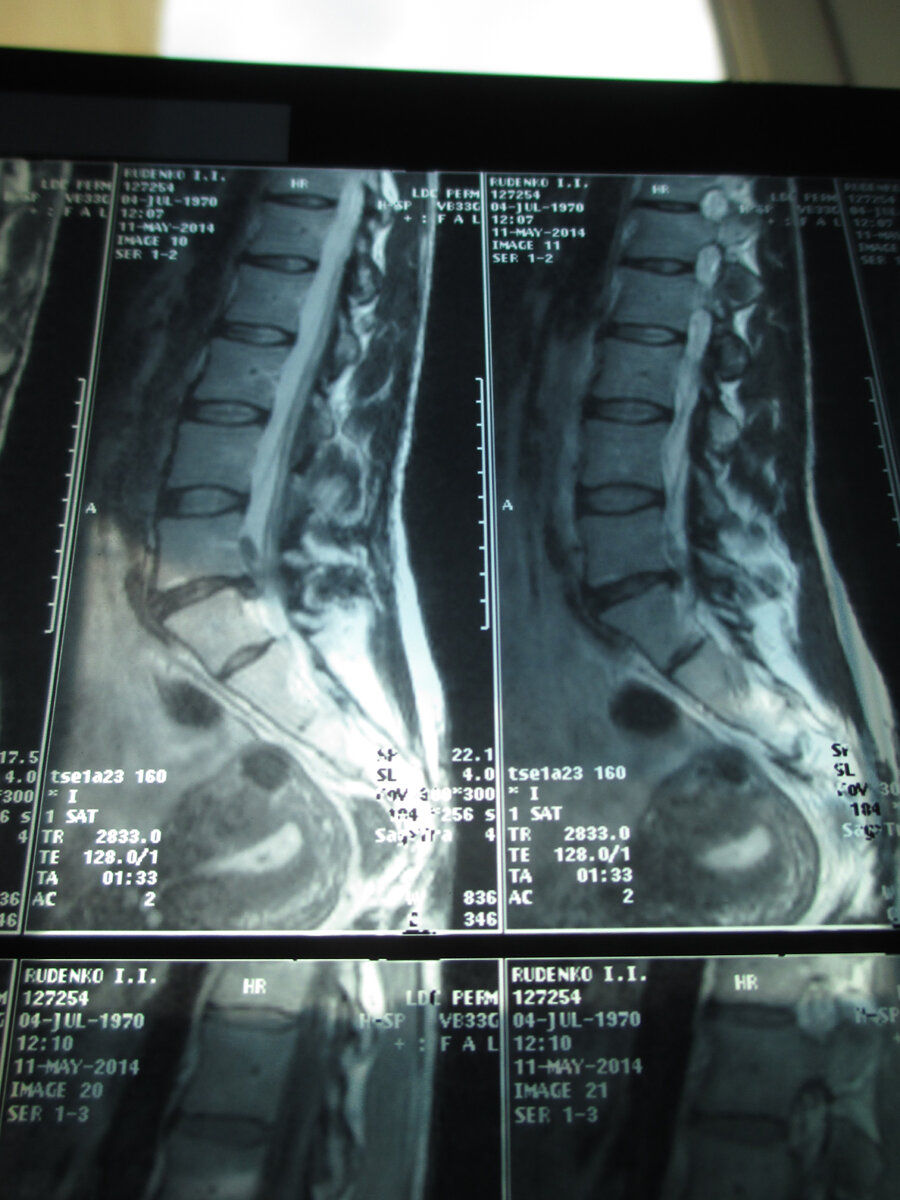

Если у вас "прихватило" спину и не раз, все же порекомендую я Вам пройти МРТ: во -первых МРТ более безопасный метод исследования, во-вторых показывает не только костную систему, но и мягкие ткани. Можно посмотреть высоту межпозвоночного диска и имеющиеся протрузии,(выпячивания) или даже грыжи, также возможность обследования позвоночного канала, так как имеет место быть сужение позвоночного канала и даже спинальный стеноз.